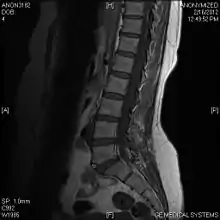

Limbus vertebra

A limbus vertebra is a bone tubercle formed by bone trauma on a vertebral body, bearing a radiographic similarity to a vertebral fracture. The anterior-superior corner of a single vertebra is the common site for this defect although it can also be seen at the inferior corner as well as the posterior or anterior margin. Anatomically, it is assumed to be an intra-vertebral body herniation of the disc material occurring during adolescent growth spurt when the ring apophysis has not yet fused. It was first described by Schmorl in 1927 and later in detail by Leif Sward and Adad baranto.

Viewed in a lateral radiograph, it appears as a triangular shaped bone fragment, not unlike an anterior lip fracture, but with softer edges.

Limbus vertebra is not always symptomatic, but severe cases may lead to more serious pathological conditions and chronic pain. In rare instances, a posterior limbus vertebra has been described causing radiculopathy due to nerve root compression.